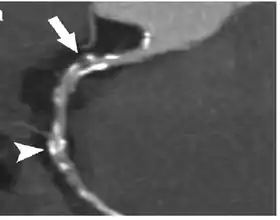

Coronary Computed Tomography Angiography (CCTA)

Computed tomography angiography (CTA), an imaging methodology using a ring-shaped machine with an X-ray source spinning around the circular path so as to bathe the inner circle with a uniform and known X-ray density. Cardiology uses are growing with the incredible developments in CT technology. Currently, multidetector CT, specially the 64 detector-CT are allowing to make cardiac studies in just a few seconds (less than 10 seconds, depending on the equipment and protocol used). These images are reconstructed using algorithms and software.